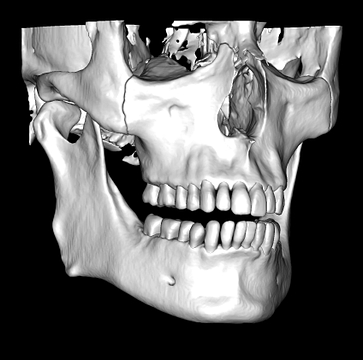

CBCT segmentation

This is one feature that actually made Diagnocat very popular early on. It was the only software that made CBCT segmentation easy. Nowadays, there are several different companies and software that carry out segmentation. Diagnocat was the first and is still arguably the best at it.

So what is Segmentation? It basically means taking the CBCT and delineating all the different 3D structures, bones, individual teeth, etc.

These can then be individually exported via the software by generating STL files from CBCT dicom data. This can be used in other dental software. Jaw STLs can be used in Modjaw (jaw motion capture) for TMJ analysis, for example. As well as in exocad to help visualize the jaws for surgical planning or guide creation.

Being able to take a DICOM file and turn it into STLs is useful for a host of different CAD/CAM indications.

- CBCT segmentation

STLs of upper and lower jaws imported into Modjaw for TMJ analysis in jaw motion. this is made possible by CBCT segmentation using Diagnocat.

The surgical crown lengthening guide was made with the aid of maxilla STL to visualize crestal bone level. Again thanks to CBCT segmentation by Diagnocat.

CBCT Segmentation into STL

Generate STL files from CBCT DICOM data.

Generate maxilla and mandible in one STL file or face, teeth, maxilla, mandible, airway, cranial base, canals as separate STL files.